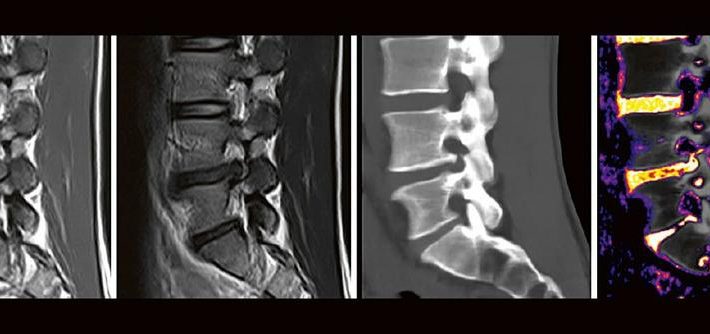

Dual-Energy CT der Wirbelsäule: Technik und klinische Praxis (Webinar | Online)

Professor Dr. med. Matthias PumbergerPD Dr. med. Torsten Diekhoff Die Dual-Energy-Computertomographie (DECT) hat für viele klinische Anwendungen bereits Einzug in die Praxis genommen. Für die Behandlung von Wirbelsäulenerkrankungen sind besonders die Darstellung von Knochenmarkveränderungen (z. B. bei osteoporotischen Frakturen) und der Bandscheibe (z. B. bei Bandscheibenvorfällen) interessant und werden intensiv beforscht. Hierdurch versprechen wir uns […]